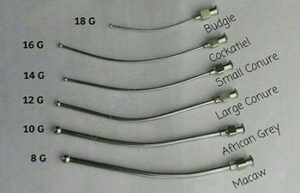

- Oral administration of the drug using gavage